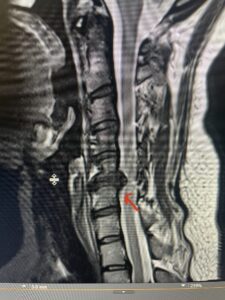

This 47-year-old male who four months prior was lifting weights developed sharp pain in his neck. After that he developed progressive numbness in his arms, neck pain and headache. He said that the right arm was worse than the left. On examination the patient had long tract weakness on the right side which included his triceps, finger extensors, hip flexors, and dorsiflexors. The patient did not have hyperreflexia. MRI (Fig. 2) demonstrated a massive, extruded disc herniation with severe cord compression. The patient because of progressive myelopathy and spinal cord compression was indicated for anterior cervical discectomy and fusion at C4-5 (Fig. 3). Patient had significant improvement of weakness and numbness post operatively.

Fig. 2a Sagittal T2-weighted cervical MRI demonstrating large C4-5 herniated disc with spinal cord compression (red arrow)

Fig: 2b Axial T2-weighted cervical MRI demonstrating spinal cord compression from C4-5 herniated disc (red arrow)